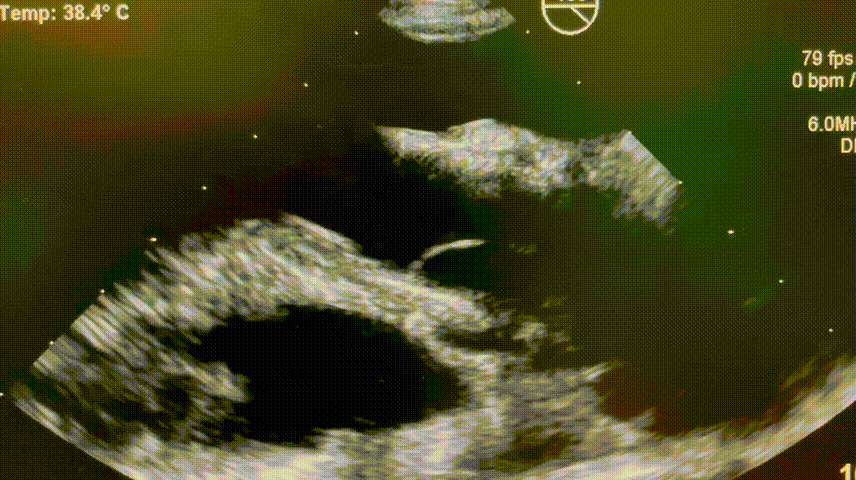

术后超声:

术后心超评估:瓣膜膨胀良好、无漏